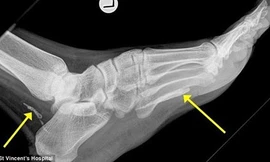

Con giun dài 1 mét lẩn phía sau mắt cá chân và lòng bàn chân một người đàn ông và đã sống trong đó 4 năm, chỉ được phát hiện ra bởi bản chụp X quang sau khi nó đã chết.